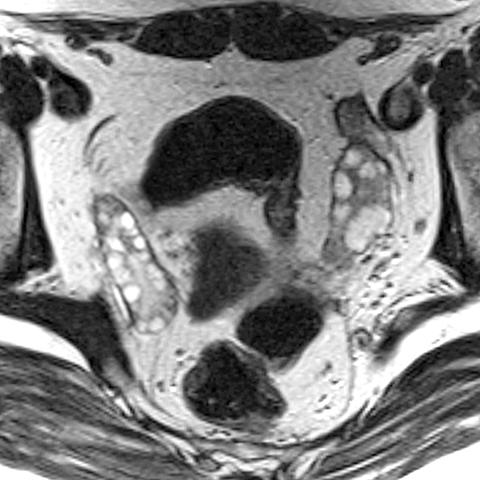

Right Ovary (T2 weighted MR) [4 of 4]